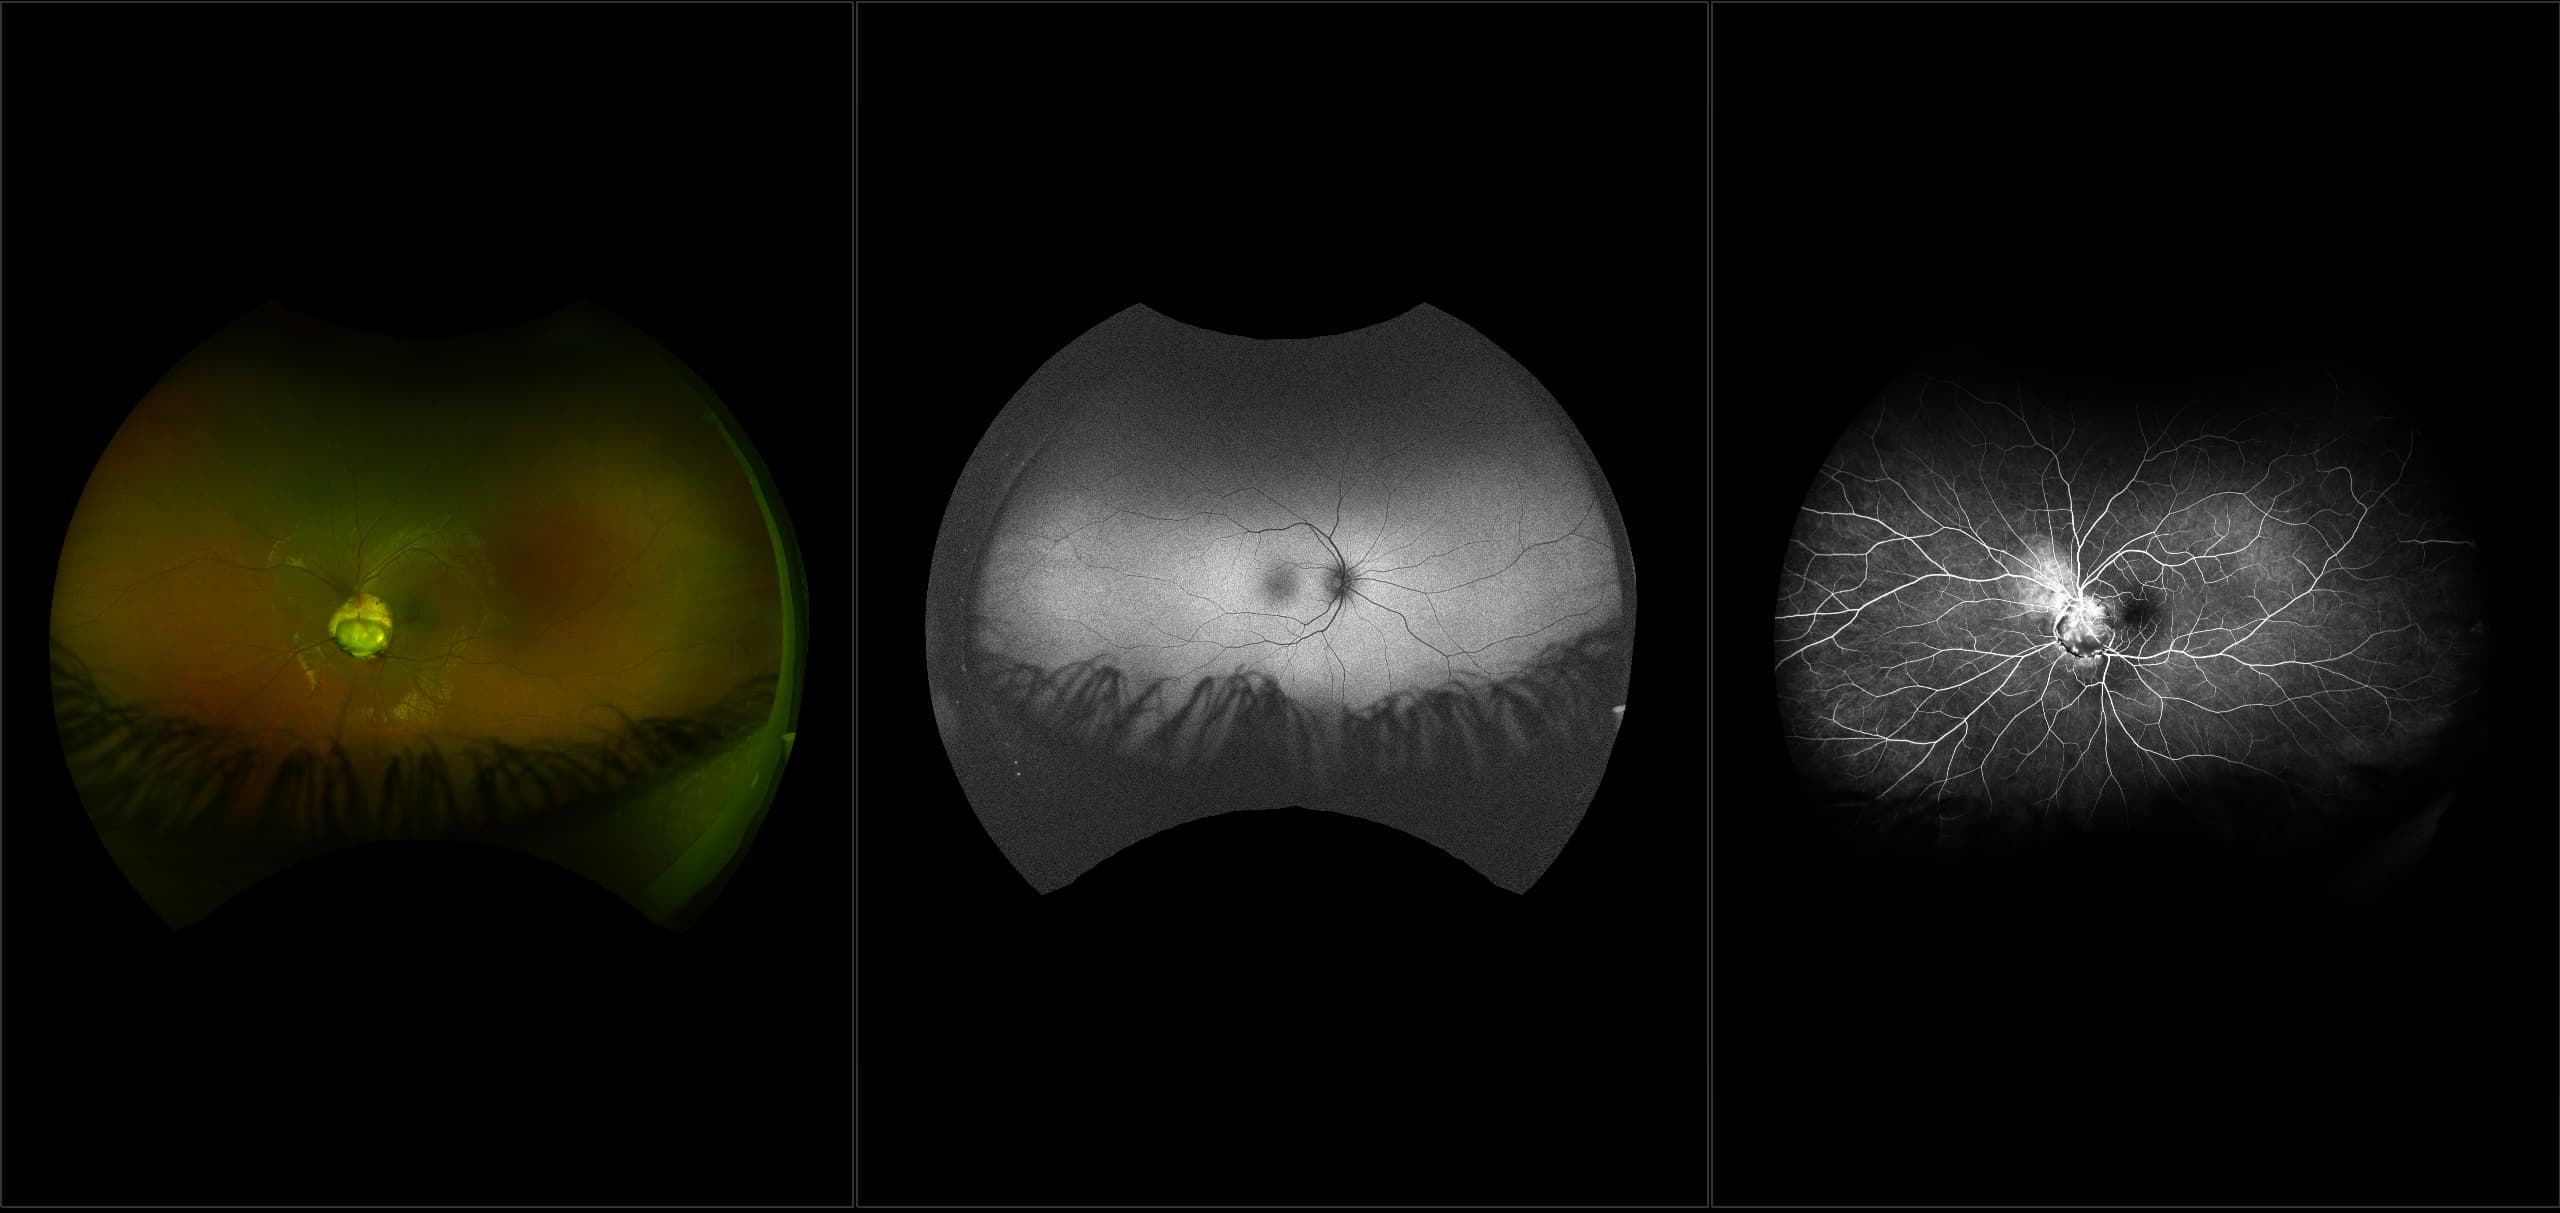

This material is designed as a searchable reference resource to support clinical decision-making. The information contained here should be used as general guidance when viewing optomap and OCT images from Optos devices. The differential diagnosis should be made under the direction of the responsible physician. These images were taken on the latest ultra-widefield optomap devices.

optomap Recognizing Pathology is searchable by pathology and/or optomap image modality. You may search by multiples of each selection. Each individual case is represented by the accompanying thumbnail image. Most cases include several different optomap image modalities. To view a full description of the case, please click on the thumbnail. Each image in the case will be made available through our OptosAdvance software which provides multi-dimensional visualization of digital images to aid in the analysis of anatomy and pathology. Support and pathology definitions can be found by selecting one of the buttons, above. Should you have questions, please complete the form below.